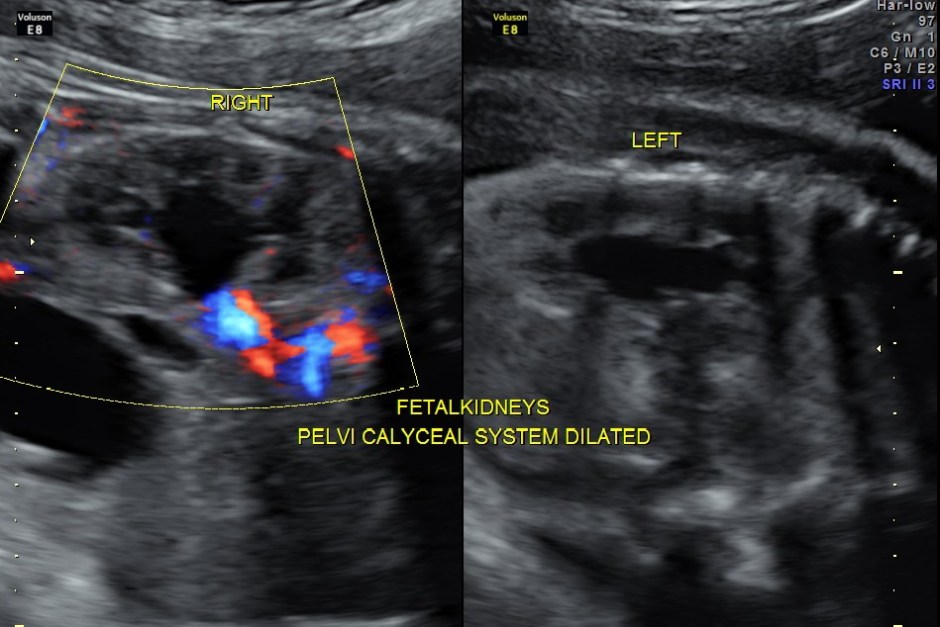

The fetus also showed bilateral pelvi calyectasis and rt ureteromegaly.